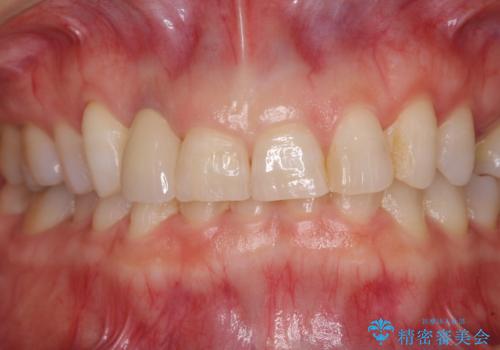

仮歯に置き換えた際に歯周外科処置を行い、歯肉の腫脹が落ち着いたことを確認してオールセラミッククラウンにて補綴することとしました。

気になっていた腫脹がなくなり、患者様には大変満足していただきました。